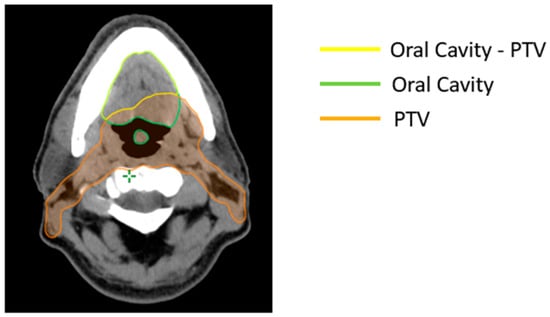

According to manufacturer suggestions, the matched OARs should not overlap with the PTV. As a result, 453 Boolean structures were created to exclude the overlap region, for all patients included in the training set (Figure 1). Therefore, the non-involved region of OARs was considered during optimization with the RapidPlan™ models.

Figure 1.

Boolean structure: oral cavity minus region overlapping with the planning target volume (PTV).